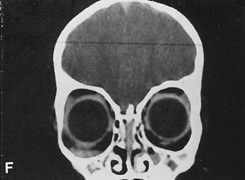

Fig. 16. A. Patient with right orbital cellulitis. B. Coronal CT scan demonstrating subperiosteal abscess formation from frontal and ethmoidal sinusitis. C. Frontoethmoidal orbitotomy incision marked for abscess drainage.

The periosteum is exposed and incised with a Freer elevator and then is reflected off the bone posteriorly. It is generally quite adherent to the curved contour of the medial canthal bones, especially at the medial canthal tendon. The anterior lacrimal crest is encountered inferiorly. Care should be taken not to damage the lacrimal sac with the elevator. The posterior lacrimal crest is visible behind the sac. Adequate mobilization of the periosteal connections to the anterior lacrimal crest gives a large area of exposure. The periosteal elevation is carried superiorly in the area of the trochlea. Elevation of the periosteum opens the subperiosteal space. Blood or pus caused by fracture or infection, if present in this space, is encountered at this point.

Indications

The frontoethmoidal medial orbitotomy allows access for a variety of procedures in the subperiosteal and peripheral surgical spaces and sinuses (Fig. 17). Its main use is for processes involving both the frontal or ethmoid sinuses and the orbit. Entrance into the subperiosteal space is obtained easily. Drainage of subperiosteal blood or pus occurs as the space is entered.

Fig. 17. Schematic demonstration of areas amenable to frontoethmoidal orbitotomy. Coronal (A) and axial (B) views. This approach can be used for exposure of the medial orbit, ethmoid and sphenoid sinuses, and optic canal.